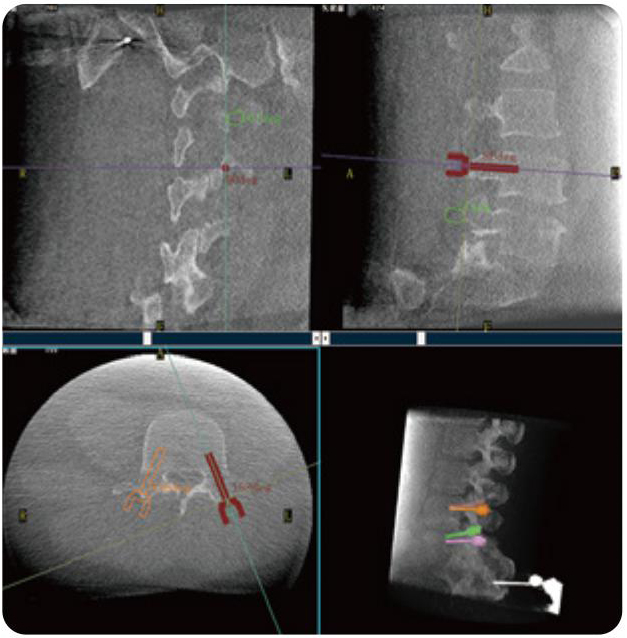

PL300B可應用于多節段脊柱外科手術,輔助醫生定位病灶部位,為脊柱外科手術(經皮椎體成形術、椎弓根螺釘內固定術等術式)提供術前手術流程規劃、入釘位置、角度可視化引導,模擬仿真入釘輔助。

PL300B搭配普愛醫療自主研發生產的平板3D C形臂,借助一體化自適應配準( 軌跡配準)技術,通過追蹤C形臂三維采集軌跡,自動完成圖像坐標建立和系統坐標配準。配準精度更高,操作步驟少,系統運作效率高。